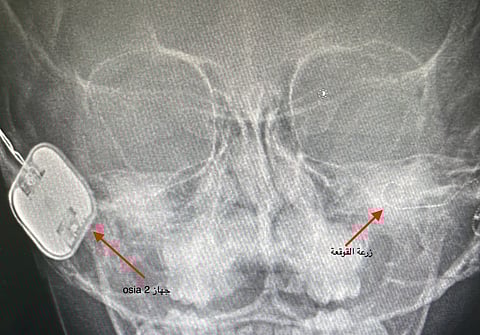

نجح مستشفى الملك فهد التخصصي بتبوك، في إجراء جراحة نادرة لطفلة وتمثلت العملية التي أجراها الدكتور سعد العنزي، في زراعة قوقعة وزراعة جهاز Osia2 معًا، لطفلة تعاني بسبب ضعف سمع توصيلي شديد الأذنين اليسرى، وصمم كلي بالأذن اليمنى.

وكانت الطفلة تعاني بسبب وجود تشوهات بصيوان الأذنين ورتق بالقناة السمعية وهي من الحالات النادرة بالعالم والأولى بأوروبا والشرق الأوسط وإفريقيا.